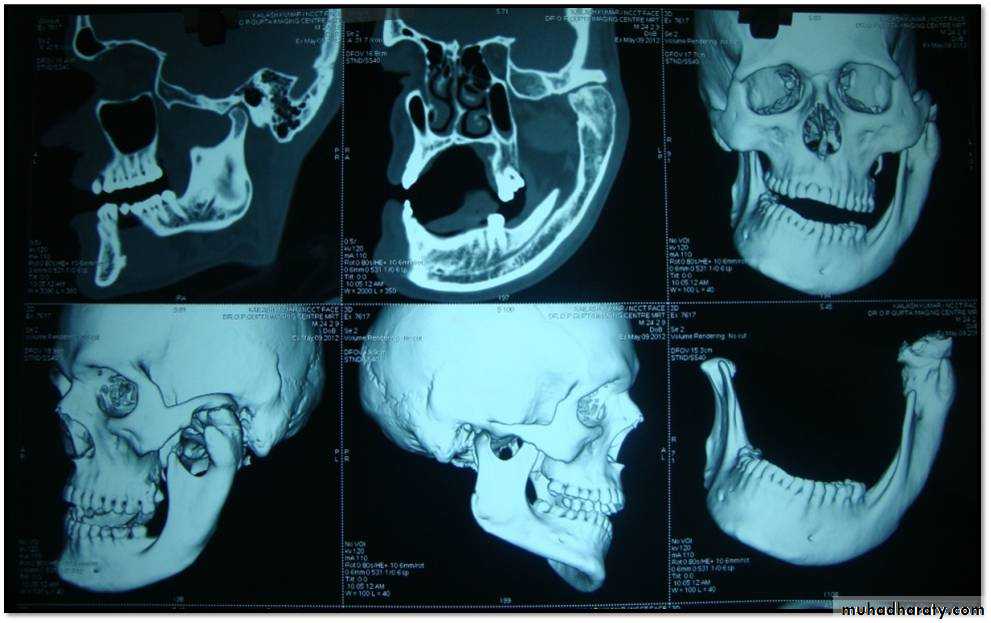

2. Cone-beam computed tomography images (CBCT)

It is usually indicated if bony changes are anticipated like in degenerative joint diseasesRadiology

Cone-beam computed tomography images of temporomandibular joint showing morphological variation of the mandibular condyle. A- Normal (coronal view); B- Flattening (coronal view); C- Erosion (coronal view); and, D- Osteophyte (sagittal view)

50Cone-beam computed tomography images of temporomandibular joint showing morphological variation of the mandibular condyle. A- Normal (coronal view); B- Flattening (coronal view); C- Erosion (coronal view); and, D- Osteophyte (sagittal view)

Radiology